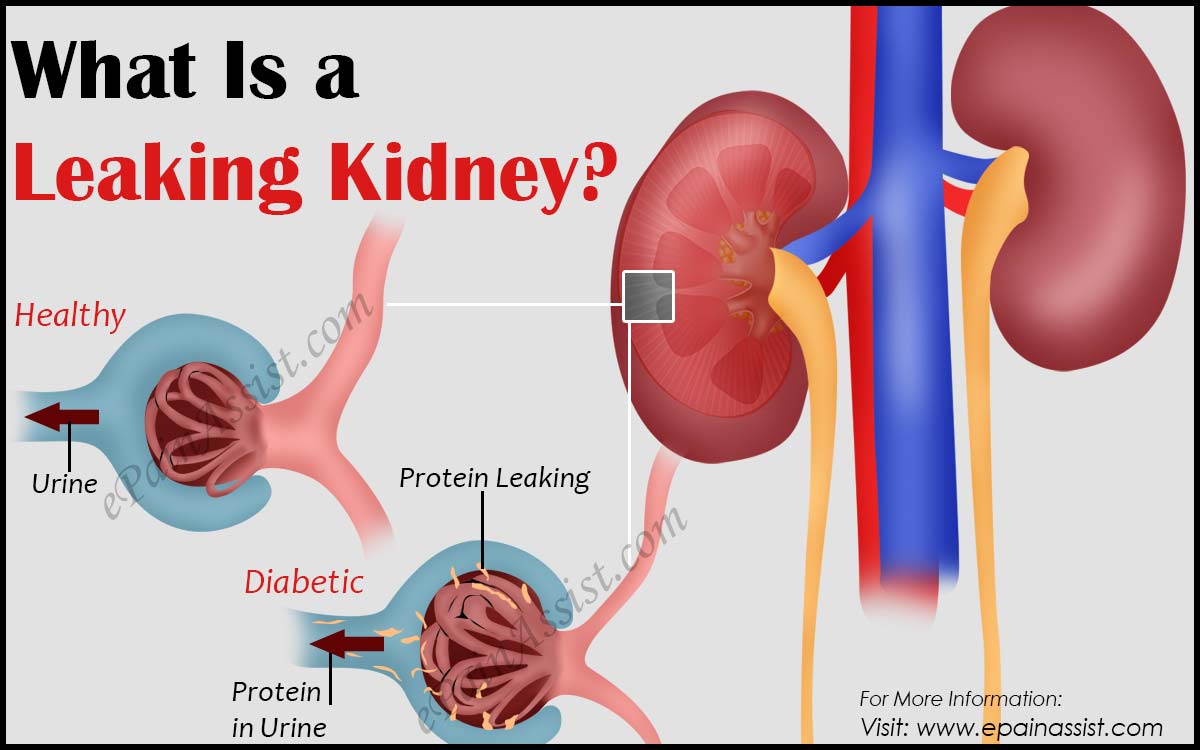

کلسیم و فسفر که برای تشکلی استخوان لازمند کمک می کنند مواد. کلیه ها با تولید ادارد در دفع مواد زاید تعادل الکترولیتی تنظیم هورمونی تنظیم فشار خون و هوموستازگلوکز نقش دارند. آناتومی کلیه انسان در بدن انسان به این شکل است که کلیه ها دو عضو لوبیایی شکل در دستگاه ادراری بوده و به دفع مواد زائد به صورت ادرار کمک می کنند. یکی از مهم ترین وظایفی که کلیه ها در بدن بر عهده دارند پاک کردن و تصفیه خون از زباله هاست.